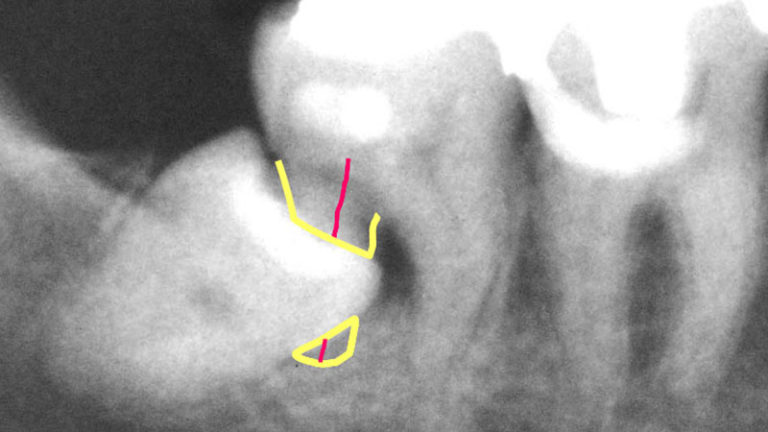

さあ、放っておくとどうなってしまったか見えますか?

なんと、親知らずによって、手前の歯の神経がちょんとブチ切られていますよね!

昔ゲームセンターであったパックマン(年代によってはわかりませんね^^:)をイメージして下さい。

パックマンに歯の神経を食べられてしまっています。

歯の神経が切られているので患者さんは噛むとものすごく痛がっています。

歯の神経血管は顎の後ろから顎骨の深い部分中を通って歯の根から入ってくるんです。

ここをちょんと切られるわけですから、とんでもなく痛いのです。

「何とか歯を残してください、親知らずを抜きますから」と患者さんはおっしゃいました。

しかし、すでに親知らずのお隣の歯(7番目の歯)の神経が切れていますから、残念ながら手遅れなのです。

なので、「親知らず」は他の歯に影響が出る前に抜いたほうが良いと私は考えています。